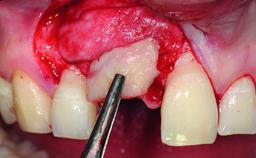

Bone Augmentation Horizontal|Simultaneous|Staged

Augmentation Materials Autogenous chips|Xenogenous|Membrane

Soft Tissue Grafting Staged